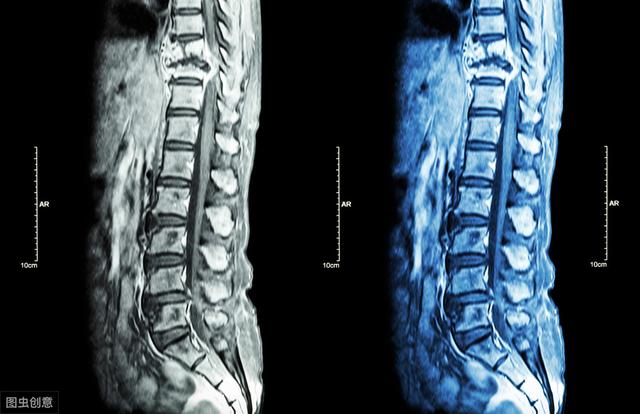

五、强直性脊柱炎是如何诊断呢?

诊断标准:45岁前发病,出现发炎性的下背痛(特征是休息无法缓解)合并晨僵且持续3个月以上。

白细胞表面抗原:抽血检查,用于检测HLA-B27基因。

九、强直性脊柱炎要与类风湿性关节炎、致密性骨炎、骶髂关节结核等鉴别(1)类风湿性关节炎:多见于女性,主要累及四肢小关节,少数累计脊椎,常为颈椎,骶髂关节很少累计,若受累到本病晚期,常为单侧发病,以骶髂关节韧带部侵犯多见,关节面下骨质疏松,继而出现小囊状骨质破坏。类风湿因子阳性,HLA-B27阴性。(2)致密性骨炎:多见于中青年女性。典型表现为在髂骨沿骶髂关节中下 2/3 部位有明显的骨质硬化,呈三角形者尖端向上,密度均匀,MRI显示髂骨为低信号,关节间隙、骶骨面和关节软骨正常,周围无骨髓水肿。(3)骶髂关节结核:多为单侧发生,常有明显全身症状。骶髂关节骨质破坏,常合并关节周围脓肿。PPT试验阳性,HLA-B27阴性。(4)其他:在诊断时有与骶髂关节炎相关如Reiter综合征、脊椎骨关节炎等,需进一步根据相关临床特征进行区别。困扰周杰伦的强直性脊柱炎,到底是什么病?骨科医生专业角度分析